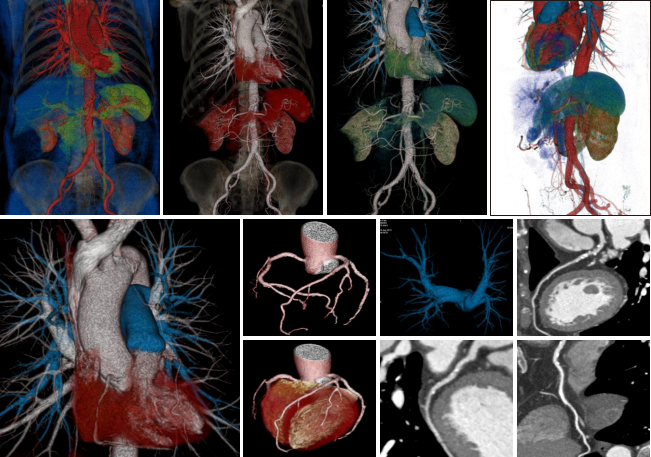

佳能(東芝)第三代超高端640層鐠黃金CT-Aquilion ONE ViSION 是一款集成DR、DSA、MRI、PET/CT等多種影像設(shè)備優(yōu)勢(shì)于一身的、最先進(jìn)的影像診斷設(shè)備。其改變了影像學(xué)的臨床診斷模式,在如下方面實(shí)現(xiàn)了臨床創(chuàng)新。

心血管方面 佳能640層鐠黃金CT依托0.275秒的掃描速度、16厘米的全器官覆蓋,旋轉(zhuǎn)1圈即可實(shí)現(xiàn)心臟成像,徹底解決了心律不齊、房顫等檢查禁忌,從而根除了錯(cuò)層偽影。同時(shí)掃描劑量大大降低,僅僅相當(dāng)于64排CT的二十分之一,自然本底輻射的八分之一。對(duì)于患有肺心病或患心臟病同時(shí)伴有呼吸系統(tǒng)疾病的病人,即使在不屏氣的情況下,也能獲得高質(zhì)量的心臟圖像。此外還可以對(duì)狹窄斑塊成分進(jìn)行分析,有效預(yù)防急性心肌梗死的發(fā)生,大大降低隱匿性冠心病的致死風(fēng)險(xiǎn)。獨(dú)有的智能冠脈減影技術(shù),可實(shí)現(xiàn)高鈣化積分病人心臟成像和PCI手術(shù)后支架病人的復(fù)查,拓展了冠脈CTA檢查的臨床領(lǐng)域。

腫瘤精確診斷 佳能640層鐠黃金CT憑借16厘米最寬探測(cè)器覆蓋,唯一在不移床的前提下實(shí)現(xiàn)全器官灌注功能成像。一次全器官灌注功能檢查,實(shí)現(xiàn)包括肝臟腫瘤、胰腺腫瘤、腎臟腫瘤等的準(zhǔn)確、早期診斷,文獻(xiàn)證明其診斷準(zhǔn)確性甚至優(yōu)于PET-CT,但檢查成本大大降低。